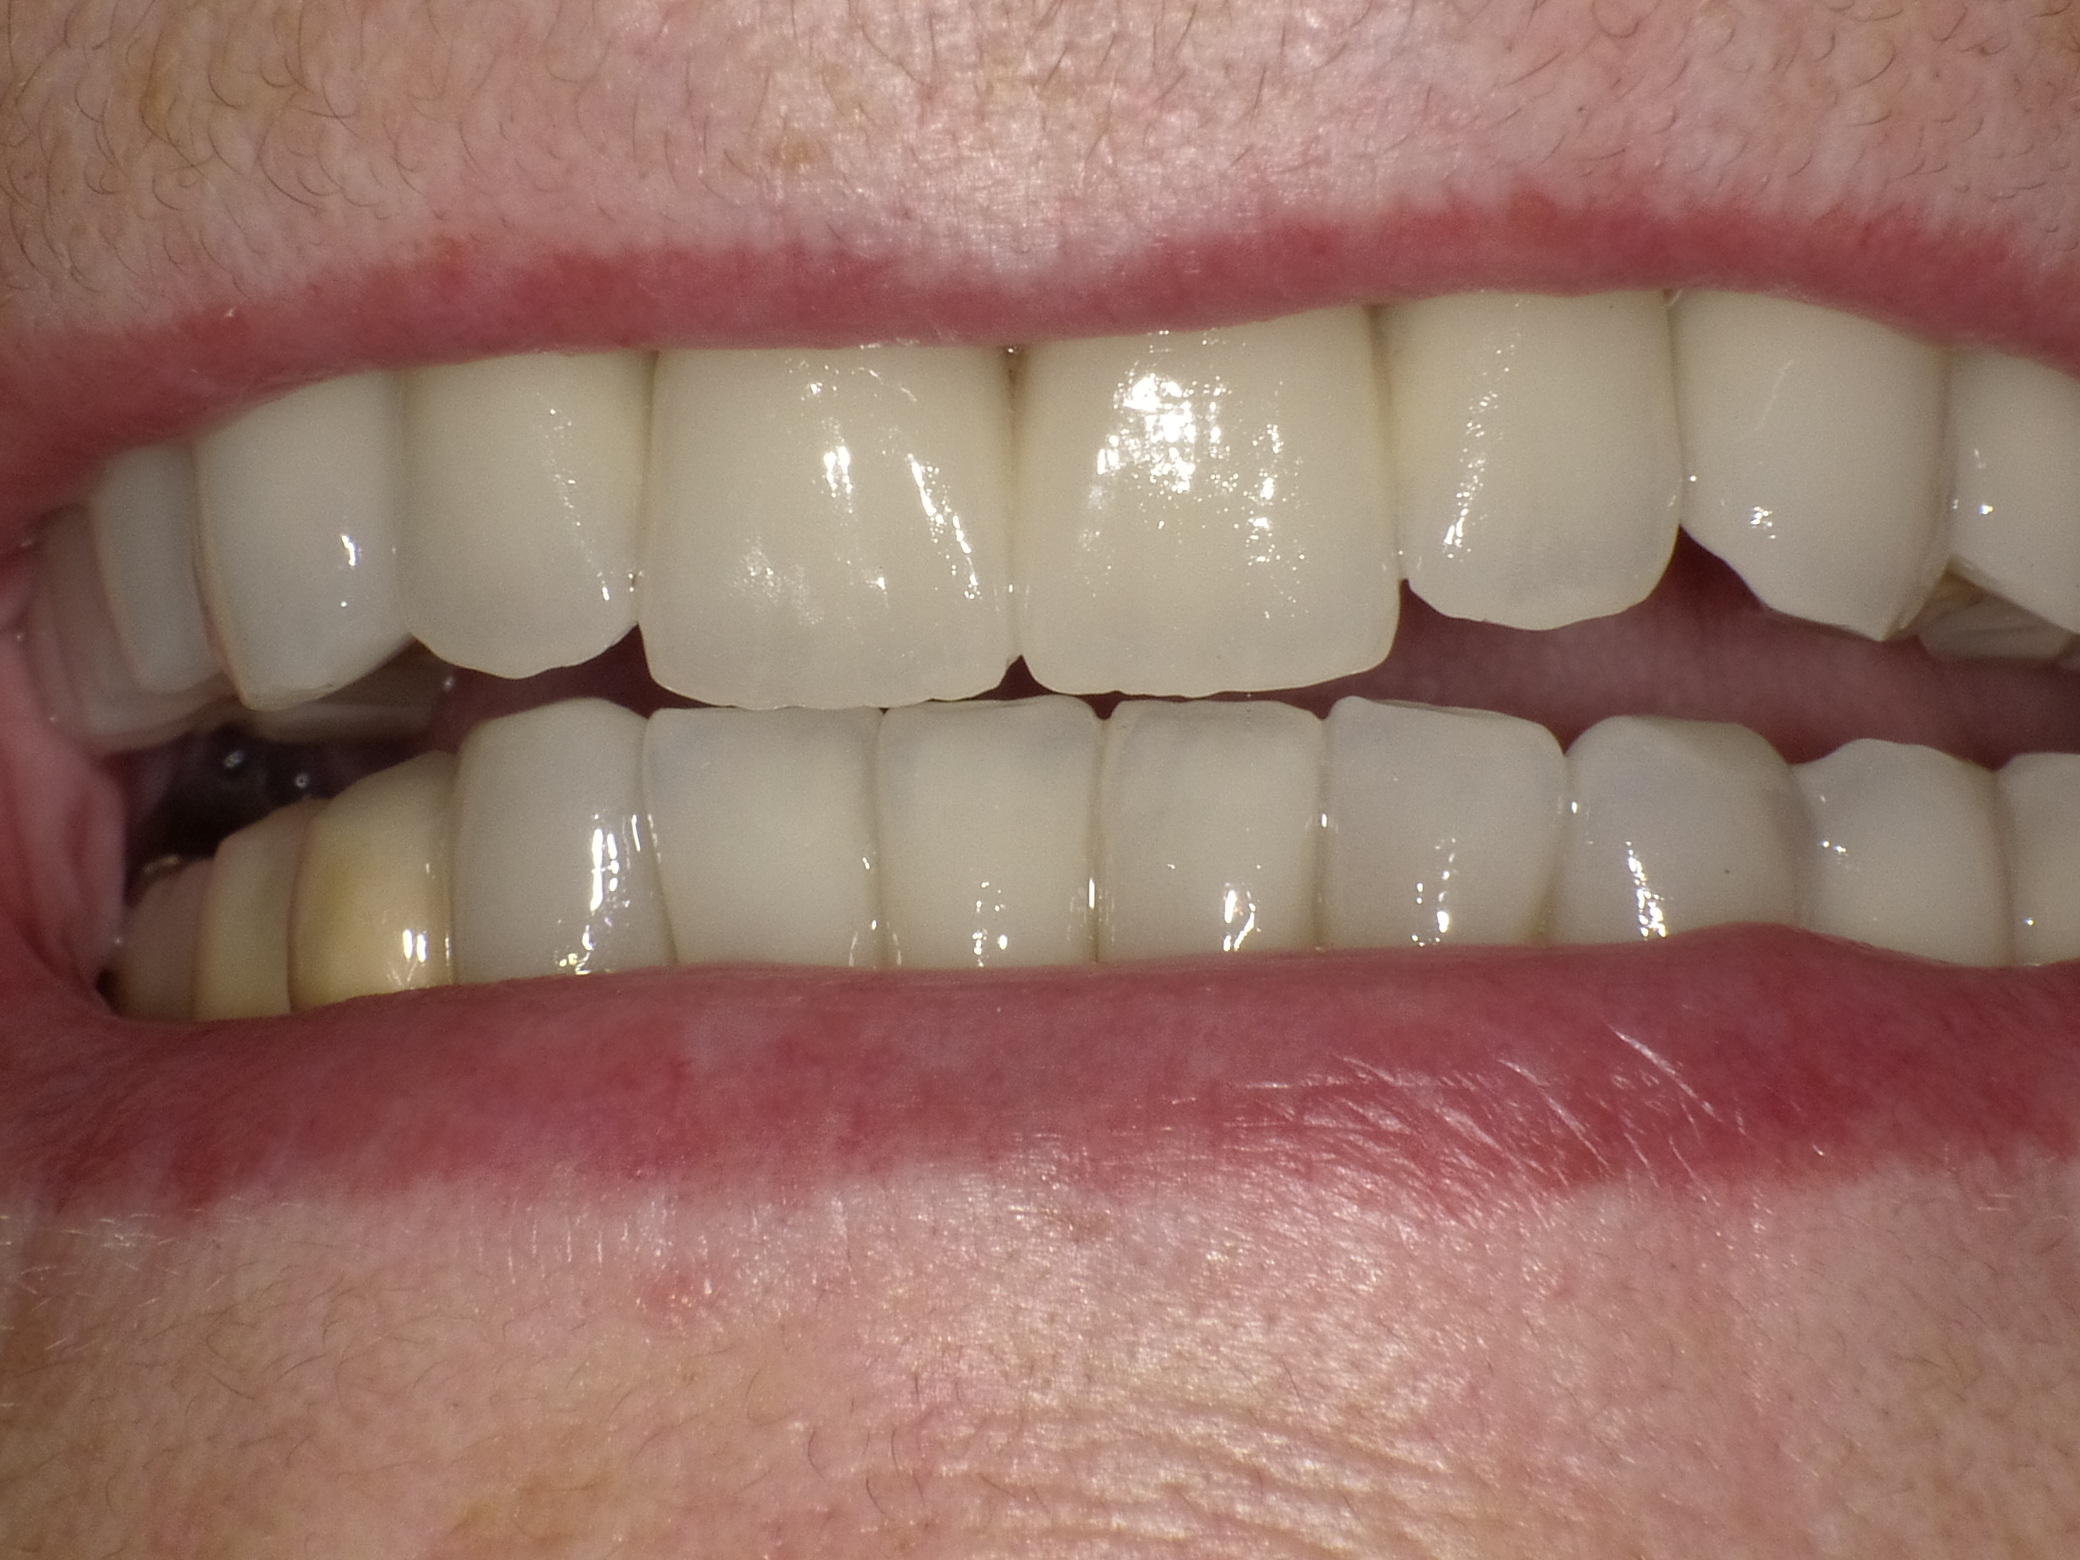

Gesamtbehandlung in Sedierung: die Seitenzähne wurden durch Keramik-Implantate (Zahnentfernungen und Sofortimplantation) mit Knochenaufbau ersetzt; anschließend Gesamtüberkronung aus Vollkeramik mit Optimierung der Ästhetik

Nachher: Gesamtbehandlung in Sedierung: die Seitenzähne wurden durch Keramik-Implantate (Zahnentfernungen und Sofortimplantation) mit Knochenaufbau ersetzt; anschließend Gesamtüberkronung aus Vollkeramik mit Optimierung der Ästhetik